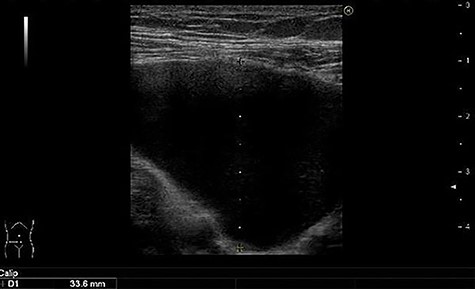

A 49-year-old woman presented with painless swelling in her right inguinal region. She had a history of caesarian section and no history of infantile inguinal hernia. Physical examination revealed a soft egg-shaped mass extending from the right inguinal region to the labia majora. The mass was seen as a protrusion when the patient was in the standing position, while it disappeared when the patient was in the lying position. Ultrasound revealed a well-defined hypo-echoic elongated mass that extended from the superficial inguinal canal, with no solid component (Fig. 1). Computed tomography (CT) showed that 55 × 34 × 95 mm oval fluid collection located at the right inguinal region near the cecum and retroperitoneum in the abdominal cavity (Fig. 2). Total colonoscopy found no mucosal abnormalities from the cecum to the rectum; however, a mass of tissue pushed the cecal wall from outside (Fig. 3). This hinted toward a large HCN, appendiceal tumor or retroperitoneal tumor; we decided to attempt a combined approach of conventional and laparoscopic methods for diagnosis and treatment of the swelling. We used three ports (12, 10 and 5 mm; Fig. 4) for our laparoscopic approach. We placed a 12 mm laparoscopic trocar into the umbilicus for CO2 insufflation of the pneumoperitoneum. Endoscopic intraperitoneal observation revealed that the mass was distant from the cecum and outside the peritoneum (Fig. 5). The tumor was large and was not completely observed using only an intra-abdominal approach. Therefore, we used a combined approach, which was the conventional method with a skin incision in the inguinal region in addition to the intra-abdominal method with laparoscopic approach. The tumor could be resected without any damage by observing from both directions (Fig. 6). We adopted the Direct Kugel Patch (ONFLEX®, C.R. Bard, Inc., USA) for the vulnerability of the posterior wall of the inguinal canal. Histopathological examination revealed that the mass contained single-layered mesothelial cells and no tumor or endometriosis. Based on imaging, histopathology and operative findings, we diagnosed her with an HCN. The patient recovered and did not have any postoperative complications, and she was discharged from hospital on postoperative day 6. She had no recurrence of hernia or hydrocele until 16 months postoperatively.